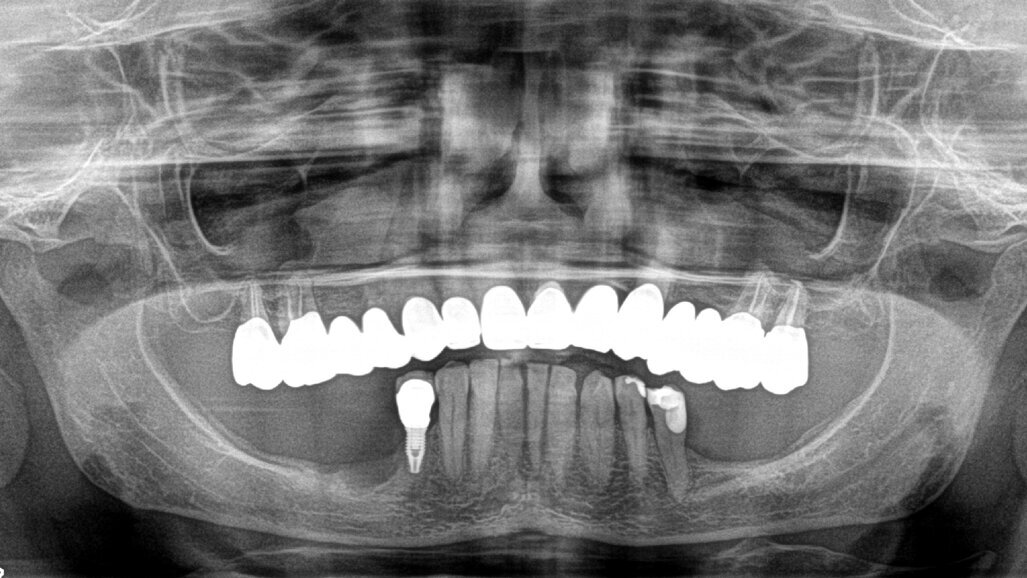

Fase protesica

Dopo tre settimane i tessuti attorno agli impianti apparivano sani e privi di infiammazione. Era presente anche una banda di tessuto cheratinizzato. Fu presa un’impronta con tecnica del cucchiaio aperto e due settimane dopo furono consegnate due corone in zirconio avvitate. Il controllo radiografico evidenziava una buona stabilità dell’osso crestale (Figg. 10-13).